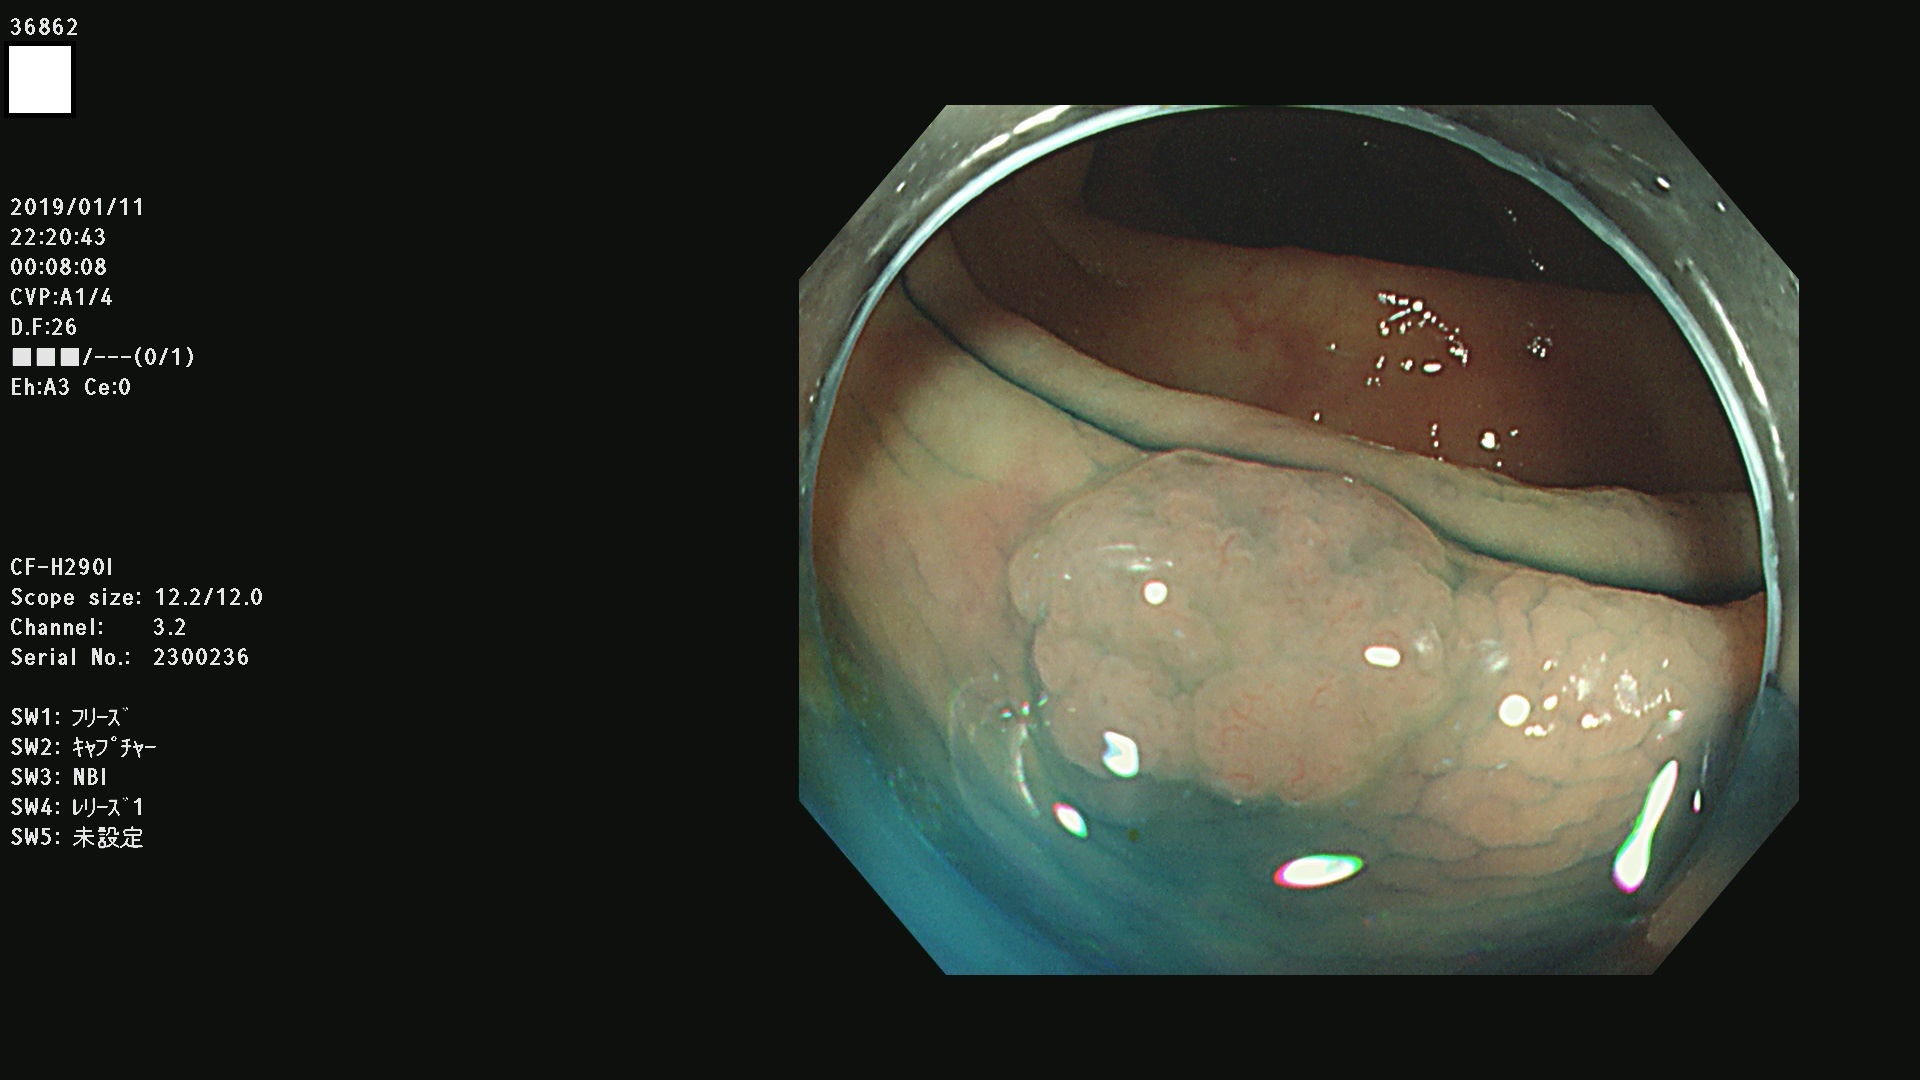

36804 36806 36807 36808 36809 36810 36811 36813 36815 36816 36817 36818 36820 36821 36822 36824 36825 36826 36828 36829 36830 36831 36832 36833 36834 36835 36837 36840 36841 36842 36845 36846 36848 36849 36851 36852 36853 36854 36855 36857 36859 36860 36861 36862(SSAPのみ) 36863 36864 36866 36868 36869 36870 36873 36875 36877 36878 36879 36881 36882 36883 36884 36885 36886 36887 36888 36889 36891 36892 36893 36894 36895 36896 36897 36898 36899

発見困難で危険性の高い平坦型病変(上記100名より抽出)